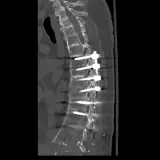

Casos totalmente interactivos con las herramientas que esperaría de un PACS: scroll, ventana, zoom, pan, mediciones, ROI y modo de pantalla completa.

• Anotaciones enlazadas

Anotaciones extensas resaltan los hallazgos clave directamente sobre los casos. Haga clic en los hallazgos enlazados dentro de la descripción del caso para saltar a su ubicación exacta en el estudio.

Desplace, arrastre, ajuste ventana y amplíe como en una estación PACS de trabajo

Aprenda con eficiencia gracias a hallazgos de imagen anotados e ilustraciones